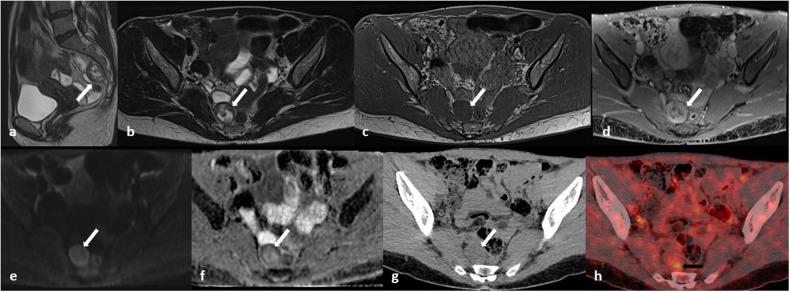

Benign nerve sheath tumors presenting as solitary retroperitoneal masses (RBNSTs) pose a complex diagnostic challenge for multidisciplinary teams regarding differential diagnosis, staging, and treatment planning. This article reviews the role played by different imaging techniques in assessing RBNSTs and elucidates their typical pathological features with a particular emphasis on the correlation between imaging and histological findings. Furthermore, some examples of retroperitoneal tumors that merit consideration in the process of differential diagnosis based on cross-sectional investigations (CSIs) are reported. The correlation between tissue architecture and appearance on imaging can help increase the accuracy of differential diagnosis with other retroperitoneal neoplasms at CSIs.

表现为孤立性腹膜后肿块的良性神经鞘瘤(RBNSTs)对多学科团队在鉴别诊断、分期和治疗规划方面构成了复杂的诊断挑战。本文回顾了不同成像技术在评估RBNSTs中所起的作用,并阐明了其典型的病理特征,特别强调了成像与组织学结果之间的相关性。此外,还报告了一些在基于横断面检查(CSI)进行鉴别诊断过程中值得考虑的腹膜后肿瘤实例。组织结构与成像表现之间的相关性有助于提高CSI时与其他腹膜后肿瘤鉴别诊断的准确性。